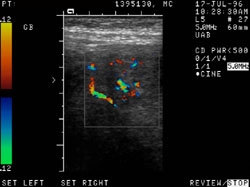

RADIOLOGY: HEPATOBILIARY: Case# 33999: GB CANCER. 88 year old female with epigastric pain, nausea and vomiting. 1. Soft tissue mass lesion arising from the anterior wall of the gallbladder and extending into the gallbladder lumen. This has the appearance of a neoplasm, most likely a primary carcinoma of the gallbladder. Metastatic lesion or lymphoma are less likely considerations. There is no definite sonographic evidence of extension of the mass outside the gallbladder nor of regional adenopathy. 2. Bilateral renal cysts, with that in the left upper pole categorized as a Bosniak type II cyst.